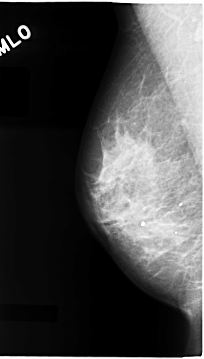

C_0065_1.RIGHT_MLO

RIGHT_MLO LINES 4664 PIXELS_PER_LINE 2648 BITS_PER_PIXEL 12 RESOLUTION 50 NON_OVERLAY